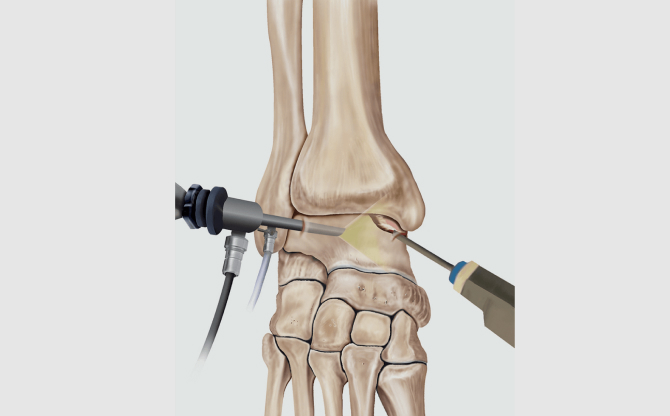

정확한 진단과 고도화된 연골 재건 치료 기술기반

비수술, 최소침습수술까지 완전한 치료 흐름